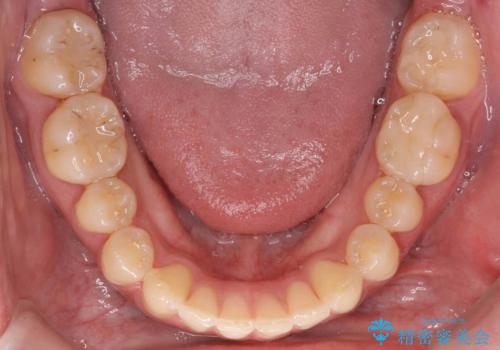

- 上下の歯のすき間を気にして来院。

患者様の歯は咬耗といって削れて短くなっていたため、セラミックでかぶせると隙間をうめるため横長の歯になりそうでした。術後の見た目は矯正の方が自然にみえるとお伝えしました。

時間はかかるが矯正治療で天然の歯の隙間をつめて歯を削らなくて済むというご案内をしたところ、セラミックでかぶせるのはやめて、矯正治療を行うことになりました。

ただし矯正を選択した場合は、治療後またすき間があかないように保定が必要になります。

それぞれ特徴がありますので十分お考えの上選んでいただき、治療結果には満足していただけたと思います。

インビザライン(マウスピース矯正)は小さな隙間を閉じるのは得意です。

ただし、上に隙間が余っている状態ですと、ただ閉じようとしても上の前歯が中に入らないと隙間が閉じないため、下の歯の位置によっては隙間が閉じ切れなくなります。

その場合は下の歯を上の前歯から離す方向に圧下したりする動きが必要になり、全体矯正が必要になります。